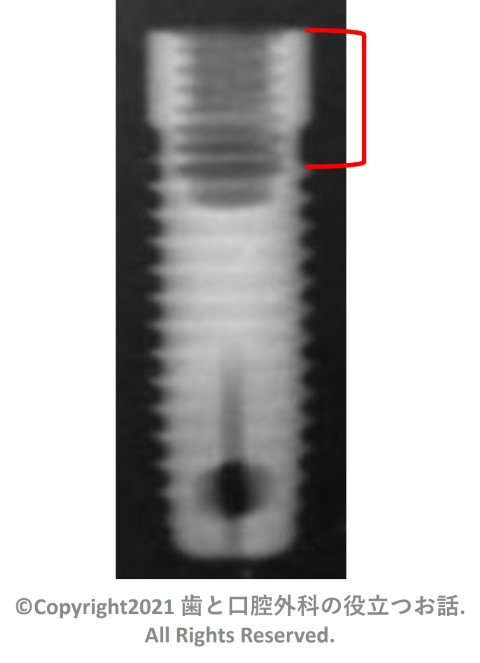

プラットフォーム部の写真

1stスレッドまでの長さ(デンタルエックス線写真での赤線部分)

長い

※定義

・長い:ティッシュレベルカラー、 1ピース、しっかりとしたマイクロスレッド等があるタイプ

・普通:プラットフォームの下からスレッドがあるタイプ

・短い:プラットフォーム無く、すぐにスレッドがあるタイプ